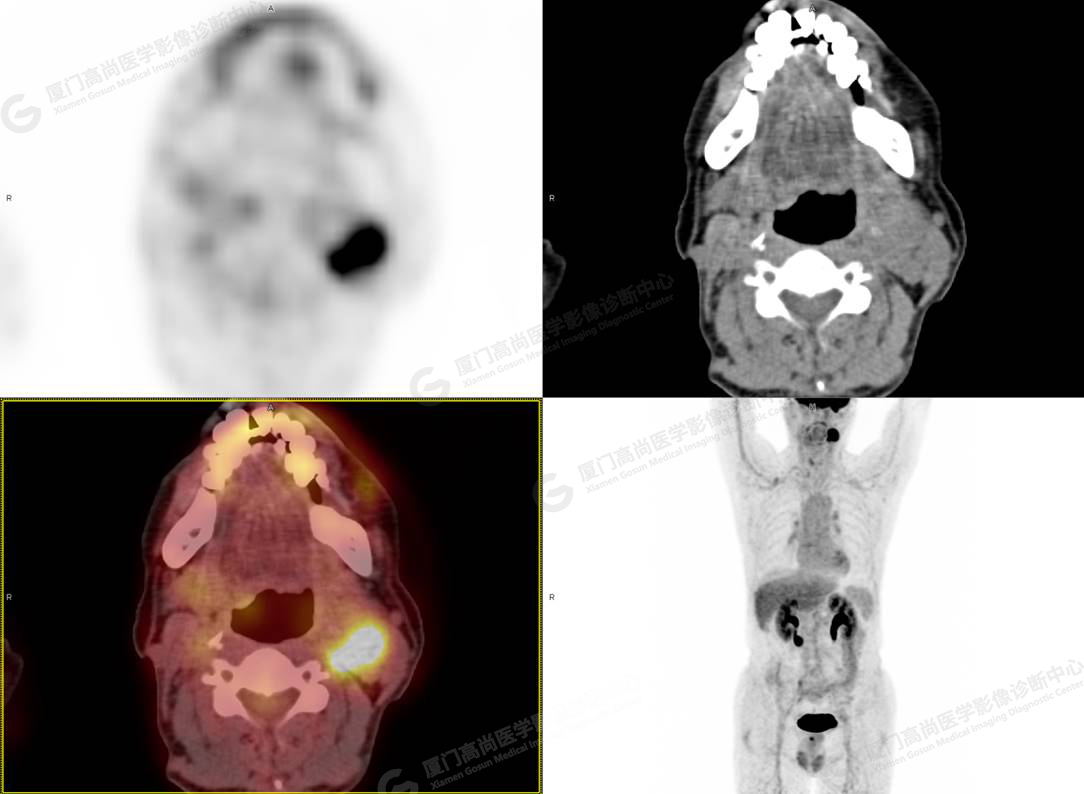

圖4

PET/CT所見:左側(cè)頸部(II區(qū))見腫大淋巴結(jié),大小約2.5cm×2.3cm,其內(nèi)密度不均,邊界尚清,放射性攝取異常增高,早期SUVmax 11.5,延時SUVmax 14.5。

影像診斷: 左側(cè)頸部(II區(qū))腫大淋巴結(jié),代謝異常增高,考慮腫瘤性病變可能性大(淋巴瘤?轉(zhuǎn)移瘤?),建議病理學(xué)檢查明確。

病理診斷:(左頸部結(jié)節(jié))副神經(jīng)節(jié)瘤。